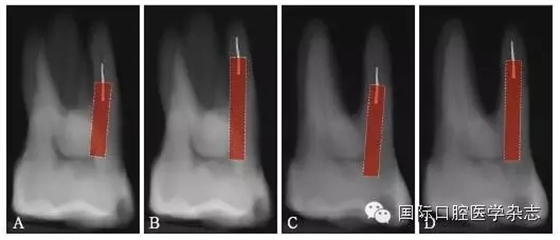

3.2.5 取出難度評估 多數(shù)情況下,如果分離器械上1/3能夠暴露,通常能夠取出。位于直根管、近根管口的分離器械較位于彎曲根管的器械容易取出。位于根管通暢部分的分離器械通常可以取出。如果分離器械位于根管彎曲附近,并且牙本質(zhì)厚度容許建立從根管口到器械冠方的通道以接近其冠部末端,而不至于產(chǎn)生穿孔等并發(fā)癥,則仍有可能將其取出。在這些病例中,都必須建立到達(dá)分離器械上部的直線通路。如果器械分離于彎曲根管的根尖部,則很難建立安全的通道,且分離器械移動可能造成器械超出根尖孔,風(fēng)險較大,通常不太可能將其去除(圖8)。

A:分離器械位于較直的根管中上部分,較容易取出;B~D:分離器械位于根管彎曲之下或彎曲根管近根尖部,無法取出。

圖 8 取出難度的評估